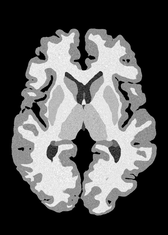

4.2 Registration to a 100 micron ex-vivo brain MRI volume

To showcase the efficacy of our method on real large scale images, we register a 250 in-vivo MRI image (Lüsebrink et al., 2017) to a 100 ex-vivo FLASH human brain volume (Edlow et al., 2019). This represents an inverse problem with more than 11.2B optimizable parameters (compared to 20M for clinical datasets), or 44.8GB of GPU memory. The entire problem does not fit on most GPUs, necessitating distributed multimodal registration. We optimize a composite transform - affine followed by a diffeomorphic mapping; details can be found in Section E.1. Multimodal deformable registration took 58 seconds on 8 NVIDIA A6000 GPUs, which is unprecedented at this resolution. Fig. 6 shows qualitative results, highlighting the ability to register highly detailed structures such as cerebellar white matter; these structures are not visible at macroscopic scales. The resultant advantages of performing registration at this scale can allow researchers to characterize the neuroanatomy at microscopic resolutions and allow morphometric analysis of cortical layers and subcortical nuclei among other structures.